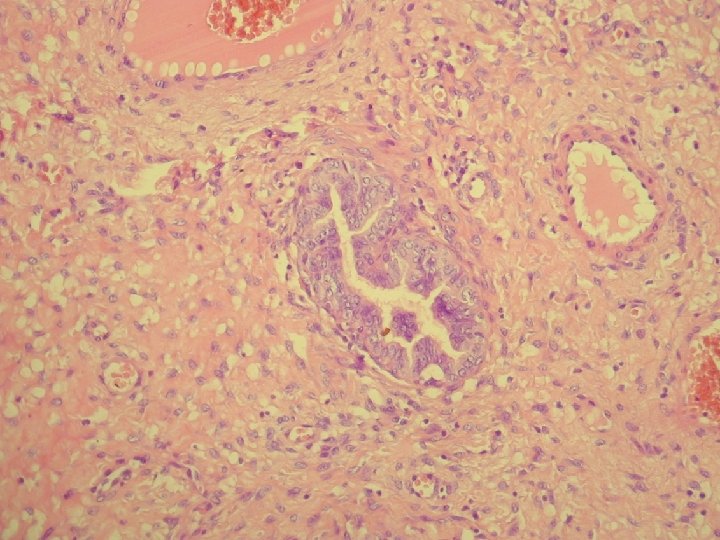

Klinicky: chronická abdominálna bolesť, dyspareunia polypoidné hemoragické masy Ø Histologicky: prezencia tubálneho epitelu s

Klinicky: chronická abdominálna bolesť, dyspareunia polypoidné hemoragické masy Ø Histologicky: prezencia tubálneho epitelu s variabilnou architektonikou v edematóznej, prevažne fibrotickej stróme Ø glandulárne prevažne tubálne inklúzie z malých epiteloidných buniek s eozinofilnou cytoplazmou, s riasinkami, sekretorické a „peg“ cells

Ø hladkosvalové vlákna a lymfoplazmocytárny infiltrát Ø bohatá vaskularizácia v retiformnej stróme, miestami aj

Ø hladkosvalové vlákna a lymfoplazmocytárny infiltrát Ø bohatá vaskularizácia v retiformnej stróme, miestami aj myxoidnej Ø Imuno: silná desmin pozit. Ø CD 34, S-100, alfa aktin, CK, calponin negat. Ø prezentovaná reaktívna stromálna proliferácia publikovaná v dvoch „case reportoch“